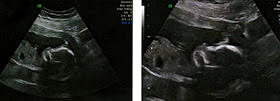

Here are a couple "baby pictures" from the day.

The kid would not give a good profile like last time, but was happy to give a nice face-front shot.

The kid would not give a good profile like last time, but was happy to give a nice face-front shot.Which, when rotated like this to get the best look at it, is a little scary!

Someone pointed out that it looks like the kid is flipping the bird.